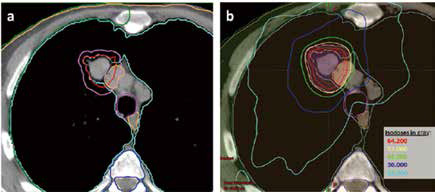

不宜手术的中央型早期老年NSCLC 立体定向放…

不宜手术的中央型早期老年NSCLC 立体定向放…

2019-04-17 15:07:04

加拿大玛嘉烈公主癌症中心Bezjak等报告,治疗不宜手术的中央型早期非小细胞肺癌(NSCLC)老年患者时,当立体定向放疗(SBRT)的最大耐受剂量(MTD)为12 Gy/f时,可带来较低的剂…